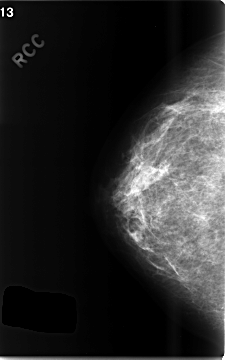

C_0503_1.RIGHT_CC

RIGHT_CC LINES 4672 PIXELS_PER_LINE 2920 BITS_PER_PIXEL 12 RESOLUTION 50 NON_OVERLAY